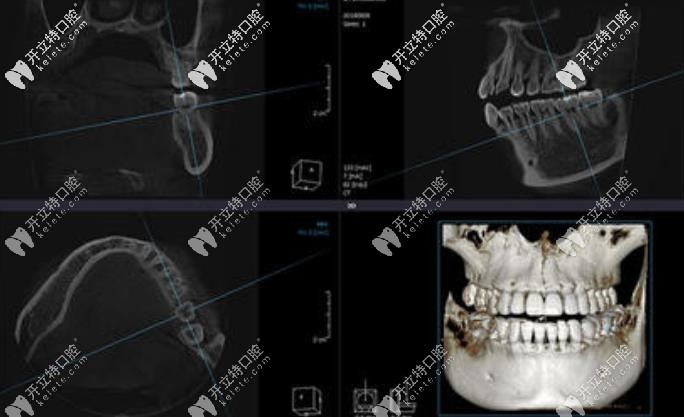

三、普蘭梅卡-MAGELLAN數(shù)字化種植設(shè)計(jì)軟件——口內(nèi)模擬種植,避開神經(jīng)血管,設(shè)計(jì)種植方案。

口內(nèi)模擬種植